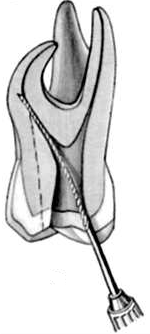

La apertura consiste en llegar a descubrir el techo de la cámara pulpar. Lo puede hacer con alta velocidad con una fresa o punta de diamante con abundante refrigeración acuosa.  Le aconsejamos que la apertura la realice con aislación relativa. Ver imagen izquierda.

La sensación al llegar a la cámara pulpar "es de caer en un vacío" ahí debe terminar la apertura propiamente dicha y debe pasar al proceso de rectificación de la cámara para el acceso a los conductos.

Usted debe rectificar las paredes y no el "Piso" de dicha cámara. Para este fin el mercado ofrece las fresas de Batt o en la actualidad la fresa Endo Z, que presentan la punta inactiva, para no producir una perforación.

Algunos autores consideran  a la conformación de la entrada de los conductos, como parte de la rectificación de la cámara pulpar. Ver imagen derecha Superior.